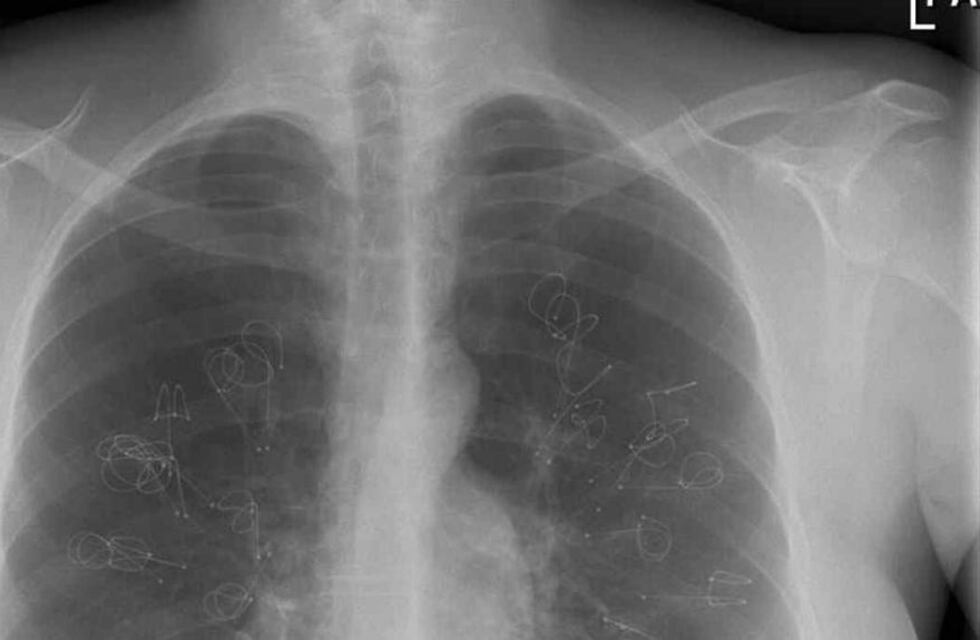

En el caso del cáncer de pulmón, se encuentra en las células de los pulmones y daña a los tejidos, afectando el sistema respiratorio. De hecho, es una enfermedad que no se detecta hasta que está en etapas más avanzadas.